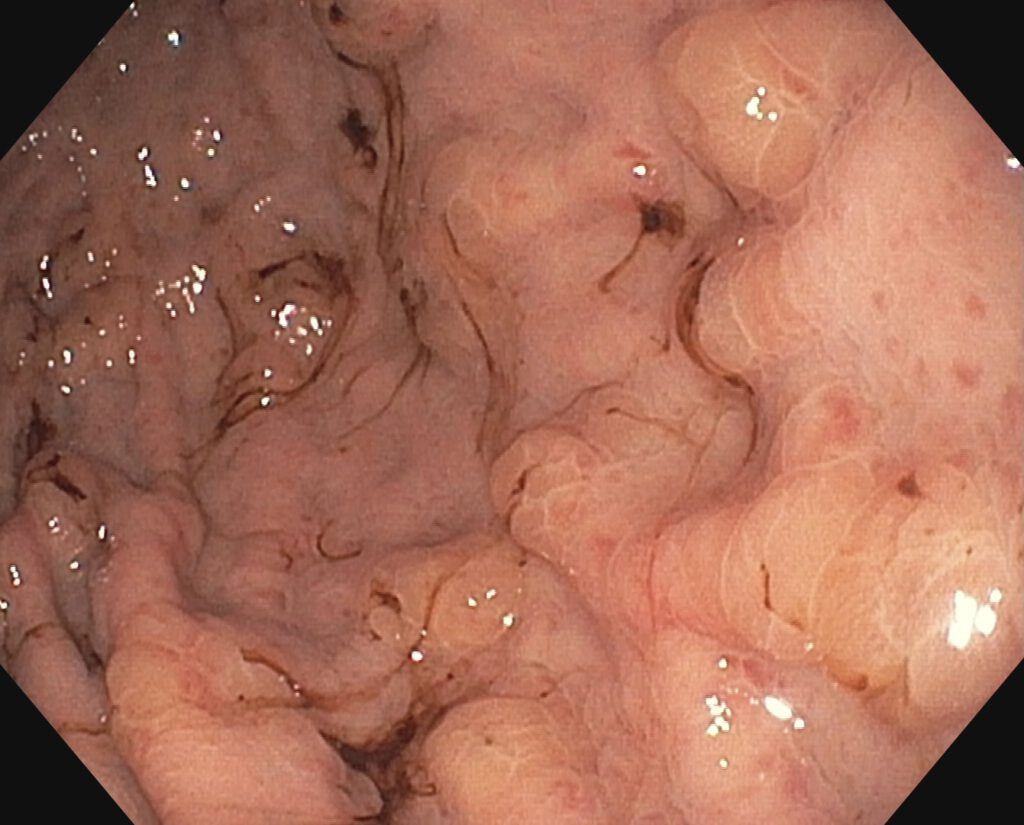

Wegen einer progredienten, transfusionspflichtigen Anämie wurde eine Ösophagogastroduodenoskopie durchgeführt. Hierbei erschienen insbesondere im Magencorpus multiple erhabene Läsionen mit teils zentraler Einziehung, umgebend fanden sich Hämatinspuren. Nach Biopsie gelang die Diagnose der Absiedlung eines malignen Melanoms.